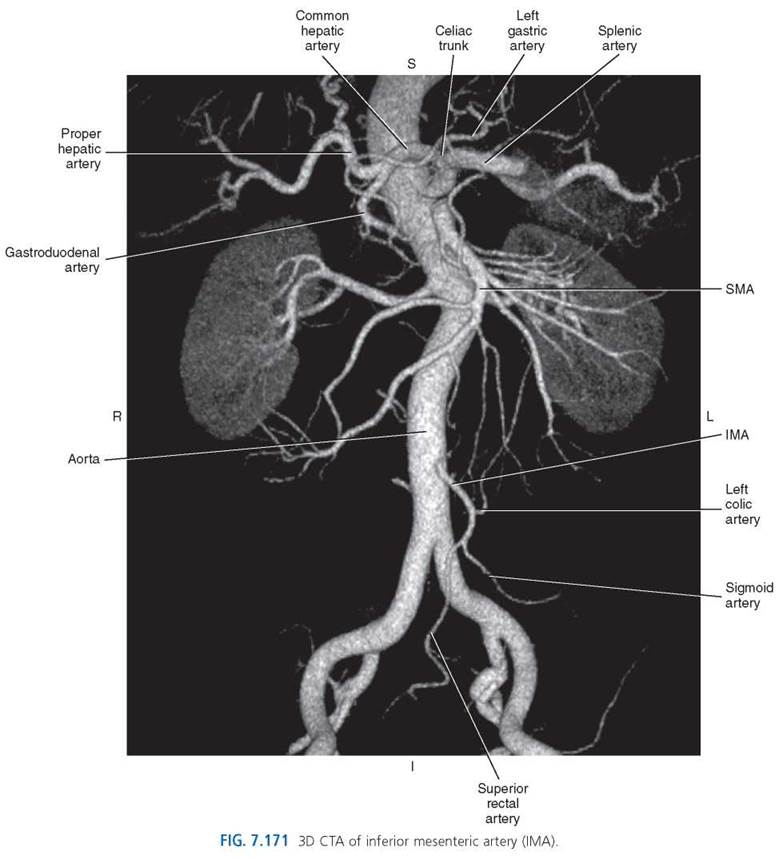

Inferior Mesenteric Artery. The inferior mesenteric artery (IMA) arises 3 to 4 cm above the bifurcation of the aorta at approximately the level of L3-L4. It descends in front of the abdominal aorta and then to the left, where it gives off the left colic artery, sigmoid arteries, and the superior rectal artery (Figs. 7.164, 7.165, and 7.169). The left colic artery is a retroperitoneal structure that passes along the anterior surface of the left psoas and quadratus lumborum muscles. It bifurcates into ascending and descending branches that supply the walls of the left third of the transverse colon and the entire descending colon. The sigmoid branches (2 or 3) course within the mesentery to supply branches to the terminal descending colon and to the sigmoid colon. The superior rectal artery crosses the common iliac artery and vein as it descends to branch and supply the rectum (Figs. 7.169-7.171).